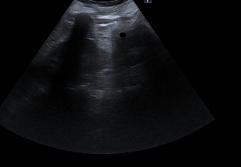

Ecografía abdominal:

Hígado y bazo normales, vesícula alitiásica, riñones normales. Páncreas con porción cefálica engrosada, contornos irregulares y ecogenicidad heterogénea, con áreas hipodensas sugestivas de edema y leve líquido peripancreático. No hay líquido libre intraperitoneal significativo.